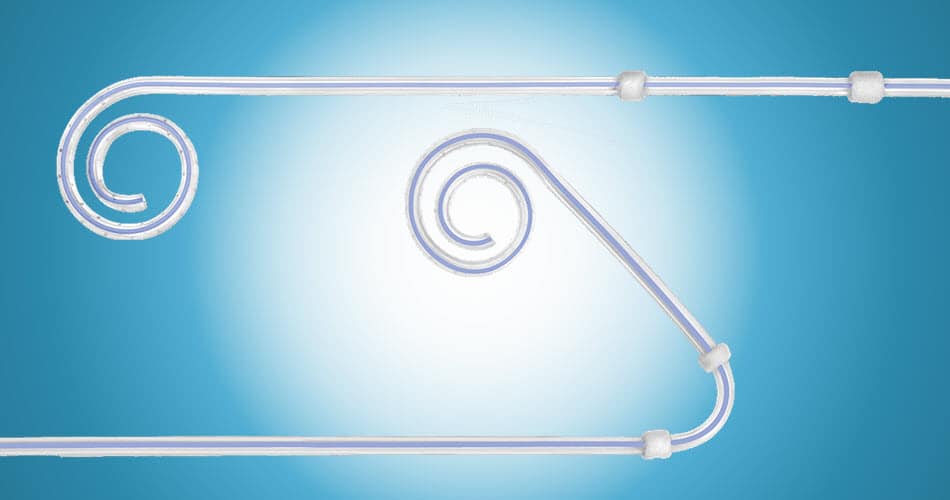

KIDNEY FAILURE

Although more women than men are diagnosed with chronic kidney disease, or CKD, men are more likely to reach kidney failure sooner.

Although kidney failure can happen to anyone, men may be more at risk compared to women due to differences in hormones and living unhealthier lifestyles.

Learn more about kidney failure and visit our Dialysis Access Solution page.

MERIT PRODUCTS